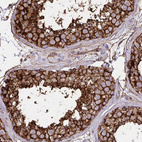

Immunohistochemistry analysis in human testis and skeletal muscle tissues using HPA030528 antibody. Corresponding MARCKSL1 RNA-seq data are presented for the same tissues.